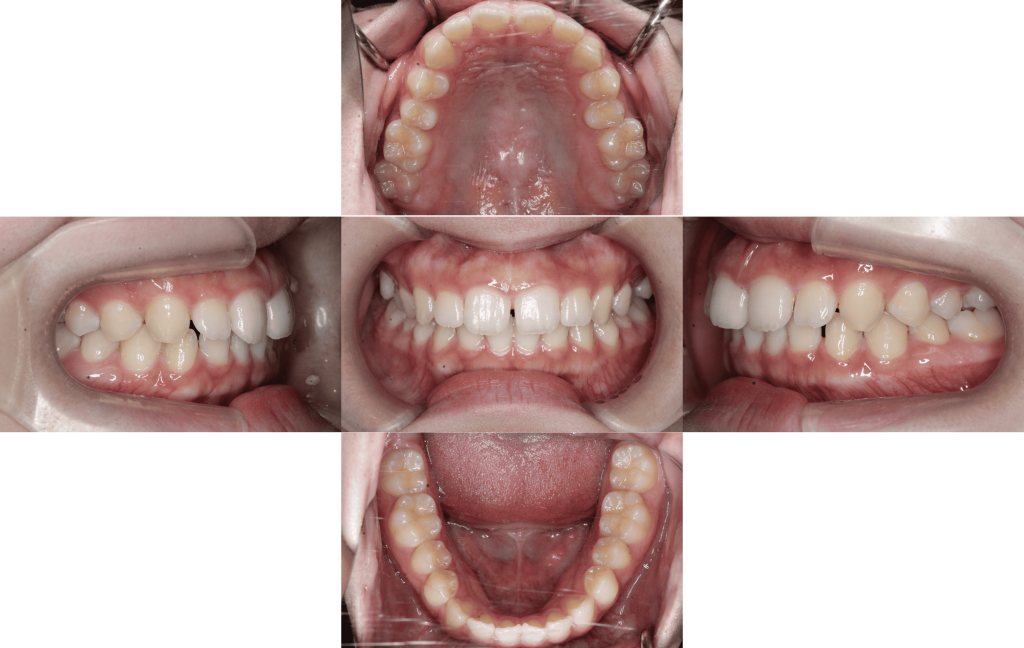

After

装置装着